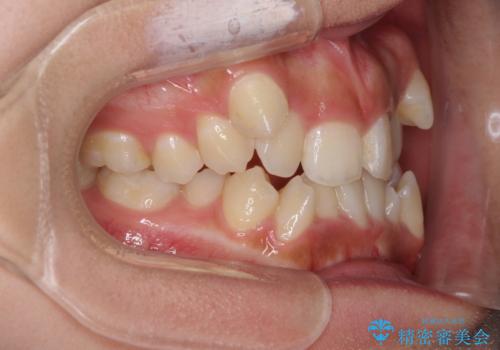

著しい八重歯が気になる インビザラインでの矯正治療

- 顕著な八重歯が気になるとのことで来院された患者様です。

インビザラインでの治療を希望されましたが、インビザライン単独では困難と判断されたため、補助装置や一部ワイヤー装置を用いて行うこととしました。

叢生が強いため、上下左右第一小臼歯4本を抜歯することとしました。